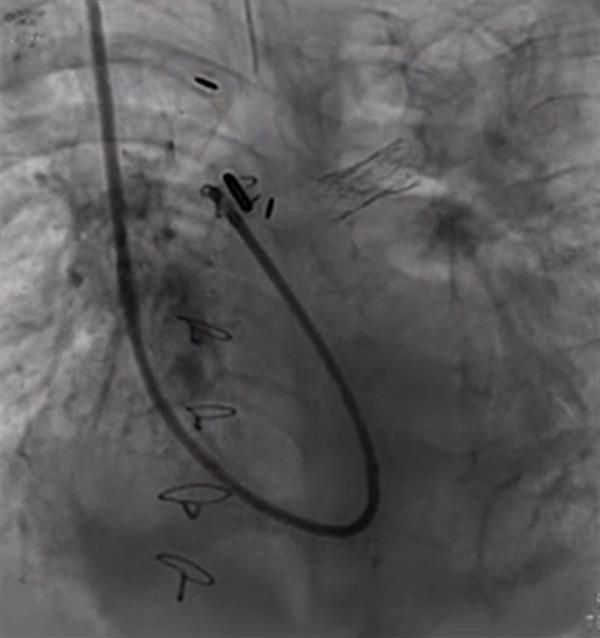

虽然Nate的血流几乎立即得到改善,他的血压下降到更健康的水平,但他仍然没有恢复。在接下来的几个月里,Nate继续增强体重,因为他需要足够的力量和体重。医生甚至可以考虑执行另一个程序。Nate接受物理治疗,他的家人尽一切可能帮助他增加体重。到2017年1月,Nate终于准备好了下一个心脏手术。1月19日,Ing博士插入了第二个甚至更小的支架,他塑造了Nate右肺动脉的3D打印模型。开放心脏手术在洛杉矶儿童医院导尿实验室进行,大量的国际心脏病学家通过实况视频观看。Ing博士和他的团队成功地开放了Nate的右肺动脉。婴儿的氧气水平几乎立即改善,相比以前,这种情况几乎没有治愈的希望。